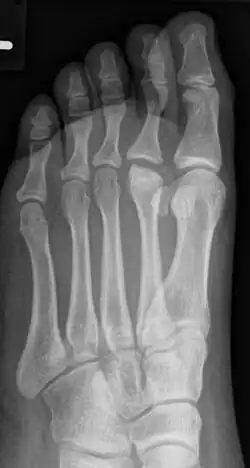

Morbus Köhler-Freiberg am 2. Mittelfussköpfchen bei einem fünfzehnjährigen Mädchen

Der betroffene Vorfuß schmerzt bei Belastung, gelegentlich treten auch Schwellungen am Fußrücken im Bereich des Mittelfußköpfchens auf. Im Röntgenbild zeigen sich erst eine Veränderung in der Knochenstruktur des betroffenen Mittelfußköpfchens und erst später eine Abflachung und eine Verbreiterung (siehe Abbildung). Auf Dauer kann die Fehlform der Mittelfußköpfchens zu einer Arthrose führen.